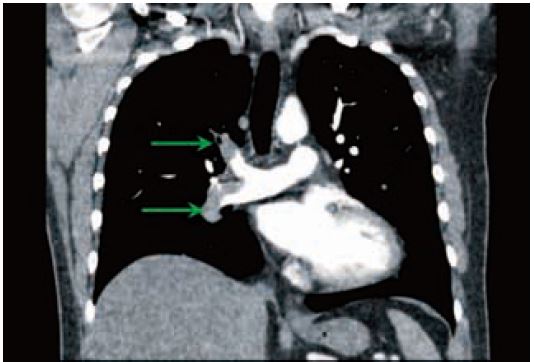

Сканування з низьким кВ генерує менше фотонів для заданого струму трубки і традиційно не застосовується для пацієнтів з високим ІМТ через погане співвідношення сигнал/шум у баріатричних пацієнтів зі звичайними системами детекторів тепер є нашою стандартною технікою КТ-ангіографії у пацієнтів з ІМТ до прибл. 35. У результаті ми змогли зменшити об’єми контрасту приблизно на 40% у цих пацієнтів, значно зменшивши ризик нефропатії, спричиненої контрастом. Крім того, тепер ми можемо набагато безпечніше проводити обстеження з ультранизькими дозами контрасту у пацієнтів із порушенням функції нирок (мал. 4-6).

Рис. 4 Звичайна ангіографія – ІМТ 26,80 kVp. 45 мл ніопаму 370 при 3 мл/с. Доза 1,3 мЗв. Множинні правобічні емболії легеневої артерії (стрілки).

Рис. 5 КТ-ангіографія з вільним диханням та одним обертом – 80 кВ. 30 мл ніопаму 370 при 3 мл/с. Доза 0,5 мЗв. Велика емболія легеневої артерії закупорює праву легеневу артерію (стрілка).

Pис. 6 ТЕЛА та розшарування аорти можна виключити в одній ротації як правило, при <1 мЗв. 30 мл ніопаму 370 при 3 мл/с.